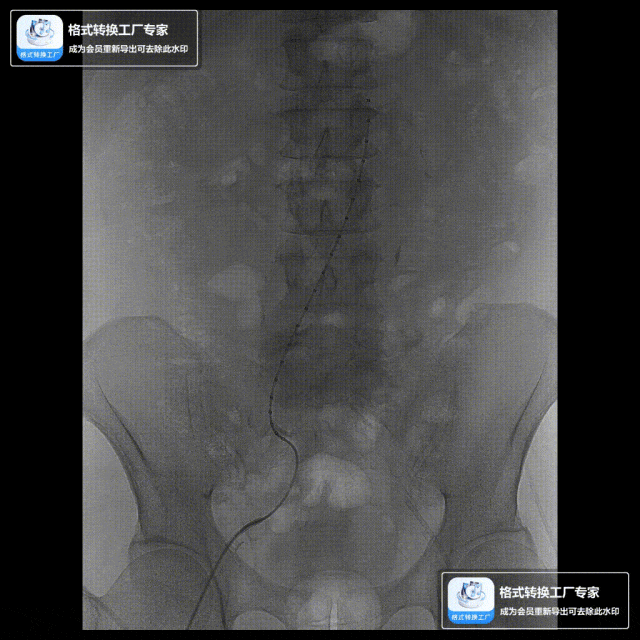

案例一(巨大成角瘤颈):患者瘤颈虽长但呈90度成角。在完成髂动脉重建后,采用Reverse技术释放主体支架。术中造影显示,支架完美贴合扭曲的血管大弯侧,术后一月复查CTA,原有的少量内漏已完全消失。

案例二(短瘤颈+梯形瘤颈):患者近端瘤颈长度不足1cm,且伴有大量附壁血栓。选用适当oversize的支架,结合Reverse技术释放,支架主体自动“寻找”并适应最佳的贴附区域,最终造影显示无明确内漏。